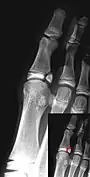

- Salter–Harris II fracture of ring finger proximal phalanx.